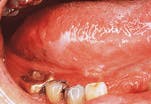

Leukoplakia

- Leukoplakia. The term leukoplakia is a clinical term that is used to describe a lesion that appears as a "white patch or plaque." The leukoplakia appears as a white, flat or slightly elevated area with a smooth or wrinkled surface.